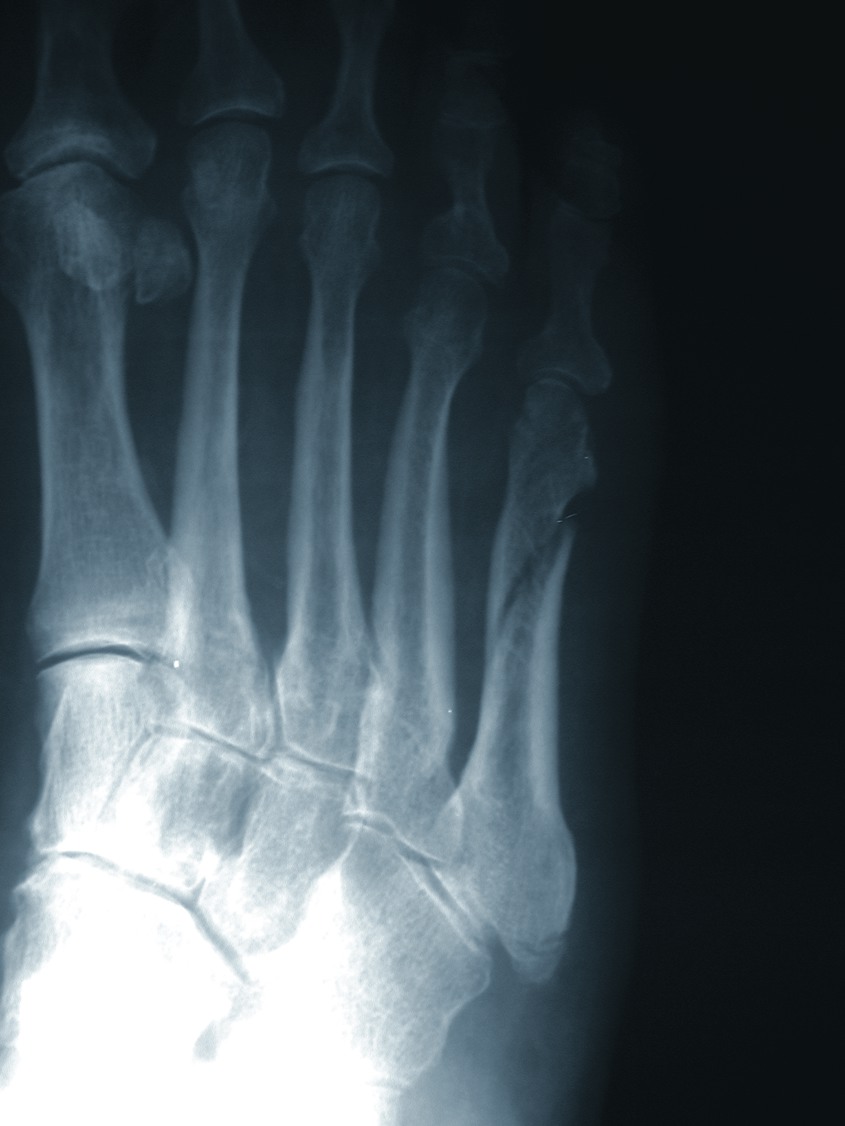

In the face of diabetes, joint stiffness and immobility can result from the glycosylation of soft tissues. This phenomenon is known as cheiroarthropathy.14,15 One would find this soft tissue glycosylation proportionate to the severity of diabetes. Clinicians can predict cheiroarthropathy based upon hemoglobin (Hgb) A1C levels. For every unit above eight, there is an increased risk of joint immobility by 250 percent.14 This type of joint dysfunction will lead to abnormal weightbearing and further complicate the aberrant gait patterns noted in patients with peripheral neuropathy. Research has further clarified that the motor deficits associated with advanced neuropathic disease results in muscle weakness and the development of abnormal mechanics in weightbearing and gait. Abnormal biomechanics yield atypical weightbearing patterns and the development of stress phenomena in soft tissue and bone. Associated ligamentous structures can become worn and elastic properties may diminish, resulting in joint instability and fractures. Newman proposed the theory that ligamentous laxity was the earliest sign of neuropathic joint disease.16 The prevailing thinking is that this laxity is the start of a vicious cycle of subtle subluxations and dislocations that would be a prelude to spontaneous dislocations of joints. If left unchecked, this would result in fractures and subsequent reactive bone formations that have become pathoneumonic for the Charcot joint. In the case of the neuropathic patient with motor and peripheral sensory loss, the lack of epicritic sensation results in a failure to recognize weakness, injury or insufficiencies of soft tissue or bone. This combined motor sensory dysfunction sets the stage for even trivial trauma to incite a dramatic propagation of inflammation, soft tissue hyperemia, resorptive bone destruction and complete loss of structural integrity that is often the harbinger of limb loss. In reviewing the historic literature, Peltier points out that the classic article written by Charcot did not correlate the development of a Charcot joint to diabetes but emphasized its relationship to locomotor ataxia.17,18 Coupling this with the fact that we are learning more and more about the effects of non-insulin dependent diabetes mellitus (NIDDM) on the dynamics of the musculoskeletal system, it stands to reason that we may be seeing more injury and reports of Charcot joint development as the number of patients with diabetes has increased in epidemic proportions over time.19 Neuropathic joints come in two varieties: hypertrophic and atrophic.5 In the wake of hypertrophic bone destruction, one will see subchondral cystic degeneration, cortical erosions, joint space narrowing, subluxations and dislocations with sclerotic changes, fragmentation of bone and heterotopic bone formations. In regard to these abnormal bone changes, clinicians typically see them in the lower extremities anywhere from the metatarsophalangeal joints to the ankle. While the Lisfranc joint is the most commonly afflicted, midfoot, rearfoot and ankle destruction is not uncommon. When it comes to atrophic bone destruction, physicians usually see this condition in the upper extremities and it typically involves patterns of resorptive change in the joint margins. For the most part, management of the neuropathic joint is guided by radiographic changes clinicians see in serial X-rays. One can cross-correlate the clinical staging of disease with radiographic changes. Immediate treatment includes the benefit of offloading the lower extremity and extensive patient education.